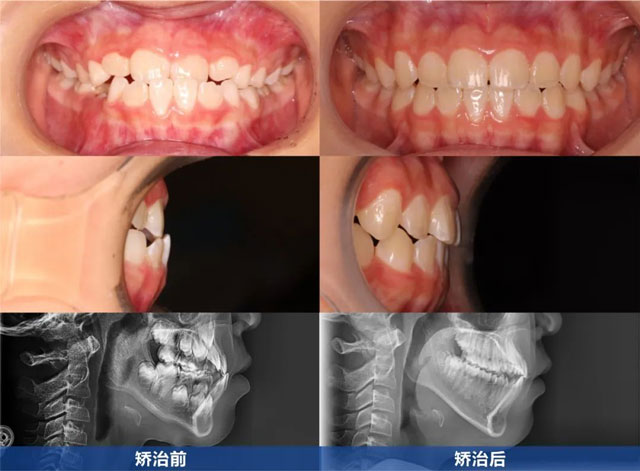

前牙反颌伴随骨性反颌治疗前后

为了帮助明明摆脱困扰,卞医生定制了一套详细的治疗方案:前期,需要佩戴面弓进行前方牵引,通过这种方式将上颌缓慢牵引至正常位置,以实现正常的覆合覆盖;后期,则使用隐形矫治器对牙列进行精细排齐。

经过两年的努力,明明的面颌形态以及骨性反颌问题均得到了显著改善,成功恢复至正常状态,覆合覆盖也达到了理想标准,原本排列不齐的牙齿如今已整齐有序。目前,明明已经顺利进入保持阶段。由于明明的换牙速度相对较快,在矫治后期,他的口腔内已全部为恒牙列,这大大降低了后续出现反弹的可能性。然而,卞医生还是特别提醒家长,若保持器佩戴不当,仍存在二次矫正的风险。